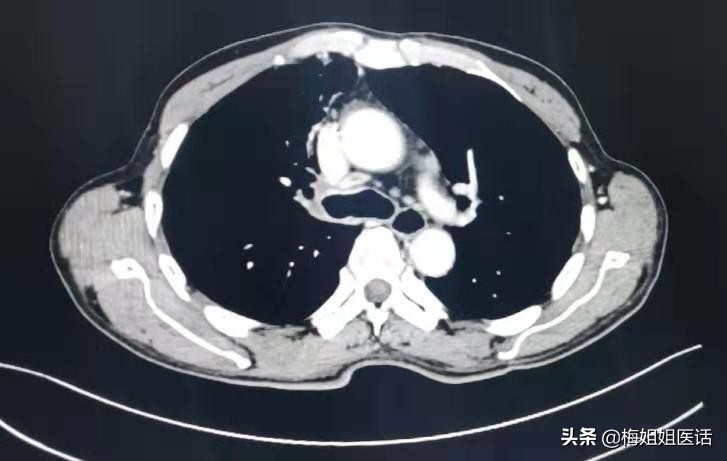

现实中,话说近日病房出院的肺癌患者,正好65岁,患者因“右胸背痛、咯血”入院,经过一系列检查,诊断右肺中央型鳞癌。

肺癌治疗前

肺癌治疗后

患者虽然年纪偏大,但心态乐观,治疗积极,家属给力,评估身体指标后难以外科手术治疗。选择行全身化疗。

化疗3个周期。胸痛咯血症状消失,状态一天比一天好。才复查评估前期治疗疗效。可以看到治疗后病变明显好转(红圈里的肿瘤几乎消失了)。病情缓解。